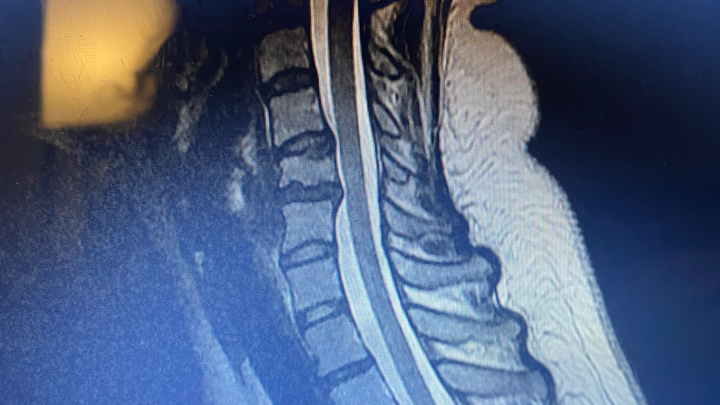

Hey all, my name is Felicia Tomolonis. This is really embarrassing, but on July 5th 2025 I was diagnosed with a concussion, which unfortunately has made my anxiety/depression/ptsd worse. It has also worsened the condition of my neck, causing more neck and nerve pain than ever before. Due to this, I’m currently out of work on short term disability. I hope to return asap and as soon as medically cleared, but with everything going on I don’t really know what else to do.

On imaging, an abdominal hernia was found that will need to be surgically repaired. It’s currently causing pain when I breathe, so working right now just seems impossible. I want to work and go back asap, because I truly can’t afford to not have help with only 60% of my earnings.